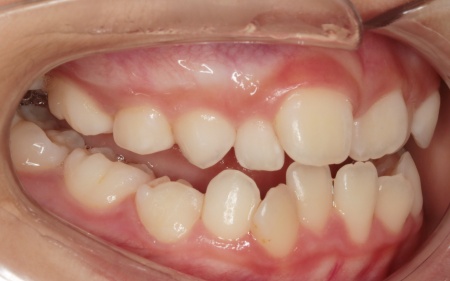

10歳女の子 顎の幅を広げる装置とマウスピース型の矯正装置で反対咬合を改善した症例

拝見したところ、上前歯が下前歯の内側に入り込む「反対咬合(こうごう)」が認められました。

詳しい検査の結果、患者様の反対咬合は歯の位置の問題ではなく、上顎の発育が十分ではないことが主な原因と考えられます。